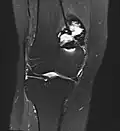

MRT-Bild (koronare PDfs-Sequenz) eines histologisch gesicherten Riesenzelltumors des Oberschenkelknochens -

Riesenzelltumoren finden sich in etwa 3/4 der Fälle an den Extremitäten und in einem Viertel der Fälle am Rumpf. An den Extremitäten sind Riesenzelltumoren weitgehend auf die Epiphyse der langen Röhrenknochen beschränkt und dort neben dem Chondroblastom der häufigste gutartige Knochentumor. Durch die Lage in der Epiphyse sind sie somit fast immer gelenknah. Die häufigste Lokalisation ist in der Hälfte aller Extremitäten-Riesenzelltumoren das Kniegelenk mit der distalen Femurepiphyse in 34 % und der proximalen Tibiaepiphyse in 29 %.[3] Riesenzelltumore können, auch wenn deutlich seltener, im Bereich der Wirbelsäule auftreten.[4]